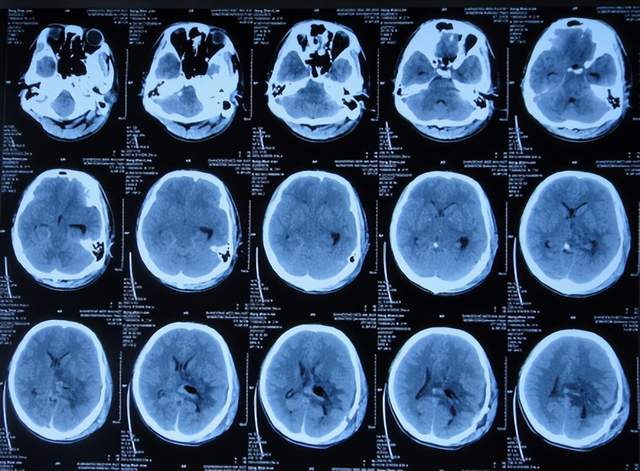

第2次出院后5个月即2022年6月初,再次出现头痛的症状,因左侧颞角再次增大,于2022年7月18日,第3次来到李小勇脑脊液科治疗。入院时:仅时有头痛。查头颅CT示左侧颞角扩张(图-33)。

图-33:2022年7月18日头颅CT

入院后3天即2022年7月21日,显微镜下颞角脉络丛切除术+分流管调整术,留置引流一根;术后查头颅CT示脑室内有2根管(图-34)。

图-34:2022年7月21日头颅CT

入院后11天即2022年7月29日(脉络丛切除术后8天),查头颅CT示引流术后状态(图-35)。

图-35:2022年7月29日头颅CT

入院治疗12天即2022年7月30日(脉络丛切除术后9天),给予拔除了原脑室腹腔分流管,查头颅CT示脑室内有一根管(图-36)。

图-36:2022年7月30日头颅CT

入院治疗21天即2022年8月8日(脉络丛切除术后18天),查头颅CT未见异常(图-37),患者身体无异常(图-38)。

图-37:2022年8月8日头颅CT

2022年8月22日(脉络丛切除术后32天),查头颅CT示颞角未见扩张(图-39),给予夹闭引流管。

图-39:2022年8月22日头颅CT

夹闭引流管14天后即2022年9月5日(脉络丛切除术后46天),查头颅CT示未见异常(图-40)。

图-40:2022年9月5日头颅CT

夹闭引流管15天后即2022年9月6日(脉络丛切除术后47天),给予拔除了脑室外引流管,当天查头颅CT示脑室基本正常(图-41);患者身体无异常。

图-41:2022年9月6日头颅CT

拔除了脑室外引流管后6天即2022年9月12日, 查头颅CT示未见异常(图-42);身体一切正常,于2022年9月16日出院。

图-42:2022年9月12日头颅CT

出院后3个月即2022年11月,在当地医院查头颅CT示无异常(图-43);本人叙述身体一切正常。

图-43:2022年11月头颅CT